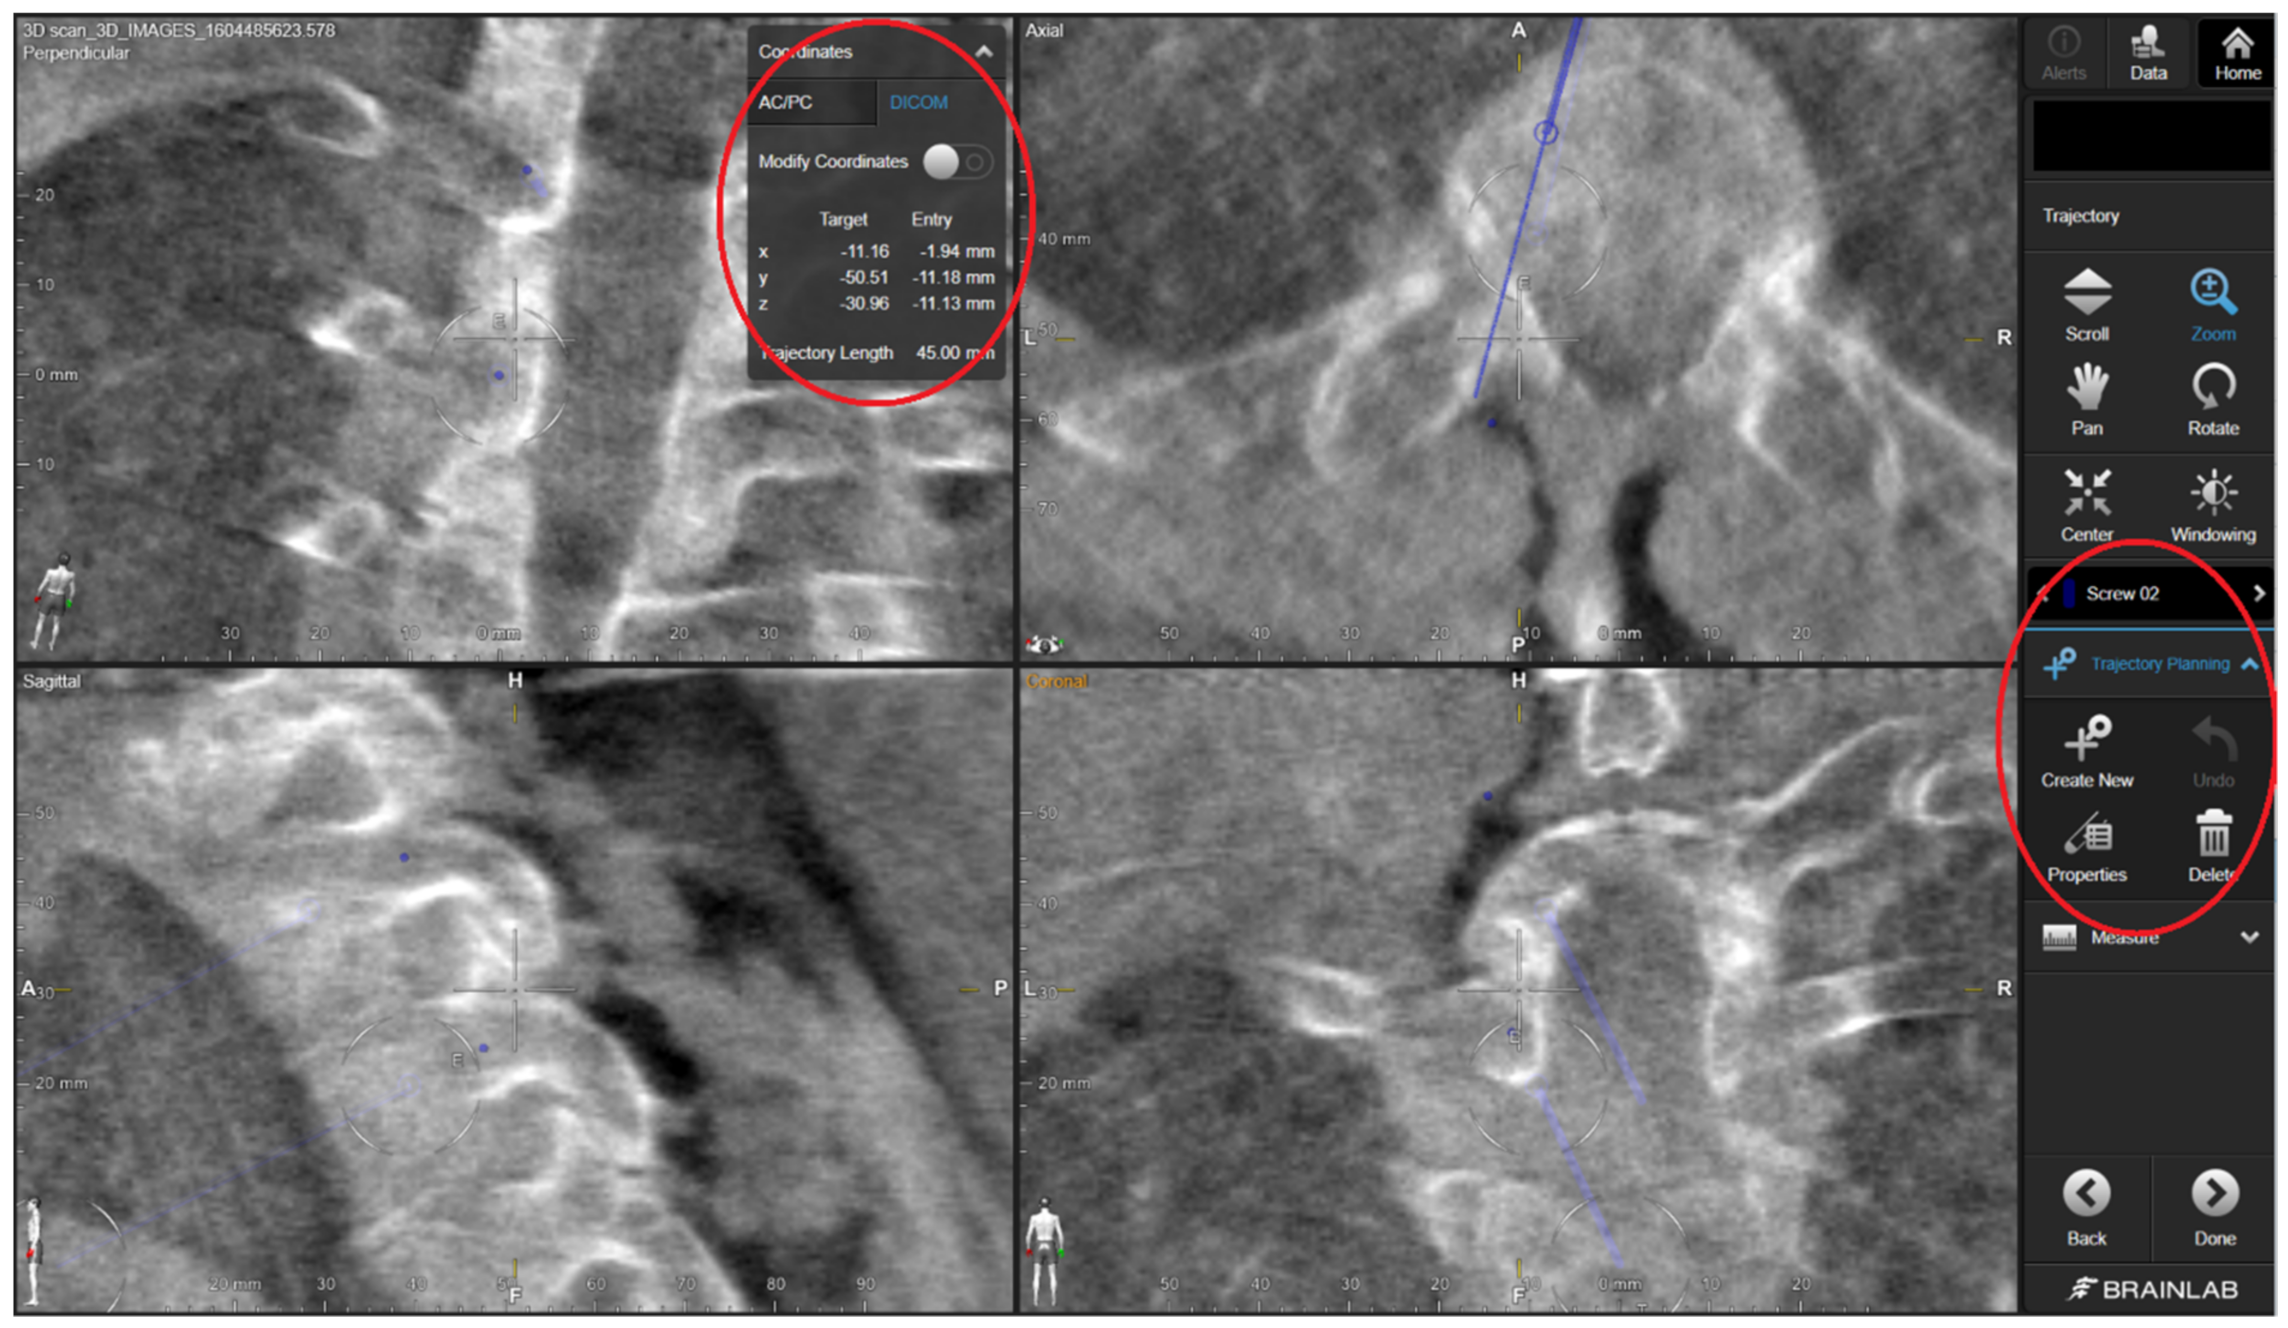

2.3. Surgical Technique

The standard surgical procedure was applied, starting cranially and continuing caudally placing screws sequentially at each level. Because randomization was concealed from the 3D specialist, the 3DPGs were designed with bilateral drill holes. Therefore, they would only fit if screws had not yet been inserted at the level of interest. Accordingly, for each level to be instrumented, the protocol stated to start with the 3DPG-assigned side followed by the contralateral CAS-assigned side. The 3DPGs were positioned after performing meticulous removal of soft tissue. Pilot holes (2 mm) were drilled at high-speed using appropriate drill stops (Figure 1). In the case of thick screws, the trajectories were enlarged/expanded using a straight pedicle probe. The study protocol ensured that the 3DPG burr hole checking was not performed using the CAS system, in order to keep the study arms separate. For the CAS study arm, the screw trajectories were created according to the standard CAS guiding procedure applied at our neurosurgical department, which consists of several steps. The steps applied in the CAS-assisted screw placement were as follows: (1) entry point identification using the CAS pointer and its marking with a ball-tipped burr, (2) definition of an optimal trajectory using the pointer, and (3) creation of a burr hole through alternated probing (or drilling for lateral mass) and pointer-based checking until the desired trajectory was achieved. For the purposes of this study, the ultimate CAS trajectory was saved intraoperatively by positioning the CAS pointer in the drill hole and storing the trajectory’s coordinates within the system. By opening the saved data using the CAS cranial module (instead of the regular spine module) postoperatively, we were able to retrieve the trajectory’s coordinates in the digital imaging and communications in medicine (DICOM) format (Figure 2). The cone-shaped pointer tip ensured concentric positioning within the drill hole. During the procedure, no navigated drill or screwdriver was used, as these tools were not part of our center’s standard procedure, nor it was available within the collection of instruments. The CAS setting comprised a mobile Arcadis Orbic 3D fluoroscopy C-arm (Siemens Medical Solutions, Erlangen, Germany) combined with a Brainlab optical navigation system (BrainLab Curve, BrainLAB, Munich, Germany).

Figure 2. Retrieval of the DICOM coordinates of the intraoperatively stored trajectories accomplished by opening the spine planning file inside the cranial module of the planning software.